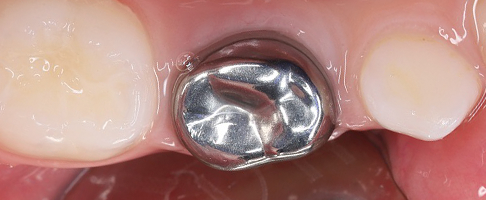

- восстановление молочных жевательных зубов коронками.

В работе доктор применяет современные биосовместимые материалы, а также изоляционную систему коффердам. Ведет фотопротокол для контроля качества работы и наблюдения результатов лечения в динамике.